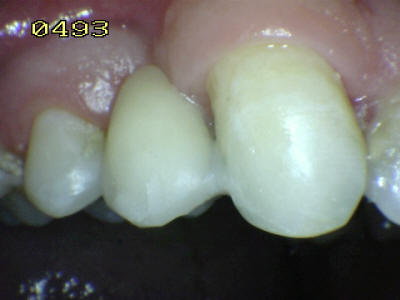

Vista palatina: Debe chequear la oclusión en céntrica y excéntrica

Vista vestibular. El matiz del póntico (flecha verde) se determino con el primer premolar (flecha marrón) Antes del tratamiento